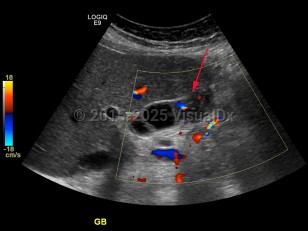

Gallbladder carcinoma

Gallbladder cancer is often diagnosed in the following ways: malignancy found at the time of cholecystectomy, malignancy incidentally diagnosed on pathologic examination after simple cholecystectomy (approximately 50% of patients), malignancy suspected preoperatively because of symptoms, and malignancy found incidentally on imaging performed for another purpose.

Patients may be asymptomatic at the time of presentation or demonstrate nonspecific findings, including right upper quadrant pain. They may have typical symptoms of cholelithiasis in early disease or with advanced disease, and may present with anorexia, weight loss, and vomiting. Ninety percent of gallbladder neoplasms are adenocarcinoma with the remainder adenosquamous, squamous cell carcinoma, small cell neuroendocrine tumors, lymphoma, and sarcoma. Papillary carcinomas have the most favorable prognosis while adenocarcinomas may extend outside of the gallbladder and invade the liver as they grow. Prognosis is dependent on histologic type and the extent of invasive carcinomatous disease.